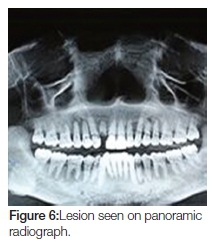

Panoramic, lateral oblique and cone-beam radiographs were taken, all of which revealed a large radiopaque lesion apical to the 48. This confirmed the presence of a sialolith (Figures 6, 7, 8, 9).

The lesion on cone-beam was seen to measure 25 x 26 mm in diameter (Figure 10). This, according to modern literature, would be considered a giant sialolith.